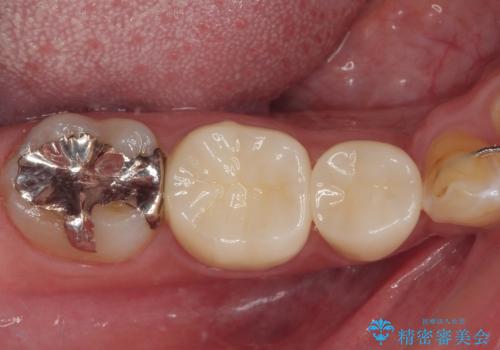

銀歯を白くしたい フルジルコニアクラウン

- 当院にて矯正治療を終えた患者様で銀歯を白くしたいとのことで来院された患者様です。神経の反応を確認し詰め物の範囲も大きいためフルジルコニアクラウンにて治療を行うことにしました。

拡大鏡視野下でメタルインレー、虫歯を除去しフルジルコニアクラウンに適した形に整えました。

歯と歯茎の間に圧排糸と言われる糸を入れてシリコーン印象材にて型どりをしました。